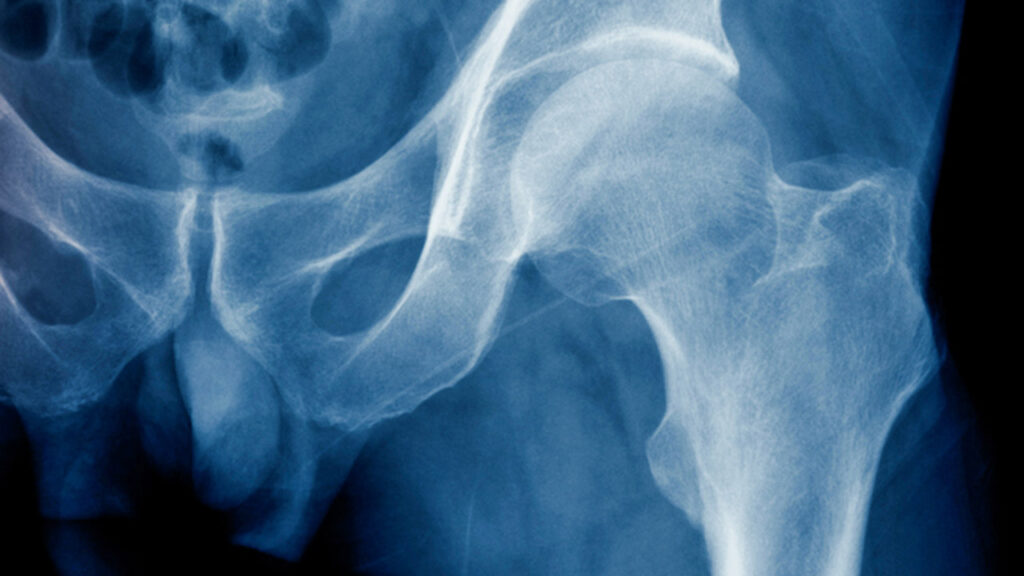

En el nivel microscópico, la arquitectura trabecular y cortical del hueso determina cómo las fuerzas se distribuyen y absorben. Las trabéculas del hueso esponjoso actúan como vigas internas que dispersan tensiones y evitan concentraciones de esfuerzo que podrían inducir fallas locales. En el hueso cortical, el diámetro, la densidad y la orientación de los osteones influyen directamente en la rigidez y la resistencia frente a torsión y flexión. Esta microarquitectura se adapta de manera continua a los estímulos mecánicos mediante un proceso de remodelado coordinado por osteocitos, osteoblastos y osteoclastos, asegurando que las regiones más cargadas fortalezcan su estructura mientras que las menos solicitadas se resorben para optimizar la economía de material.

A nivel macroscópico, la forma general del hueso y su geometría determinan cómo se transmiten las cargas a lo largo del esqueleto. Por ejemplo, la curvatura, el grosor cortical y el diámetro de los huesos largos influyen sobre la cantidad de momento flector que pueden resistir antes de deformarse. Esta dimensión estructural permite que el hueso no solo soporte fuerzas estáticas, sino también cargas dinámicas o repetitivas, contribuyendo a la resistencia a la fatiga, un factor crítico en actividades de alto impacto o movimientos repetitivos.